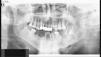

Additional TestsOrthopantomography showed an area of osteolysis of the cortical bone in the left mandibular arch, as well as other radiolucent points indicative of general mandibular involvement (Fig. 2).

Diagnosis is based largely on the clinical manifestations. Imaging studies are the main additional tests and allow the severity and extent of mandibular involvement to be determined.5